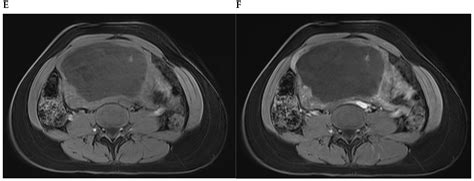

Diagnosing uterine myoma degeneration involves a combination of medical history, physical examination, and imaging tests. The diagnostic process typically includes:

• Imaging Tests: Ultrasound, MRI, or CT scans to visualize the fibroids and assess the extent of degeneration.